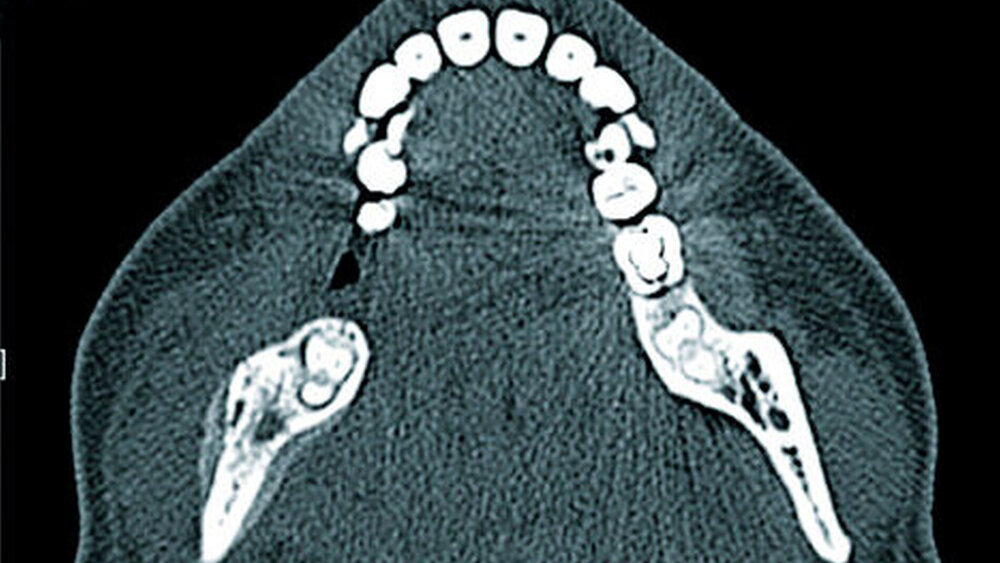

Computertomografie und digitale Volumentomografie (CT/DVT) bieten eine überlagerungsfreie morphologische Darstellung der Kieferregion mit Erfassung von Knochenstrukturveränderungen in hoher örtlicher Auflösung (Abbildung 7). CT und DVT stellen derzeit den Goldstandard in der Identifikation von nekrotischen Knochenanteilen, zum Beispiel Knochensequestern, dar. Bei zusätzlicher Gabe von intravenösem Kontrastmittel kann in der CT auch eine entzündliche Mitbeteiligung der Weichteile beurteilt werden. Eine Limitation der CT und der DVT stellen die in der Kieferregion oft vorliegenden Zahnartefakte dar.